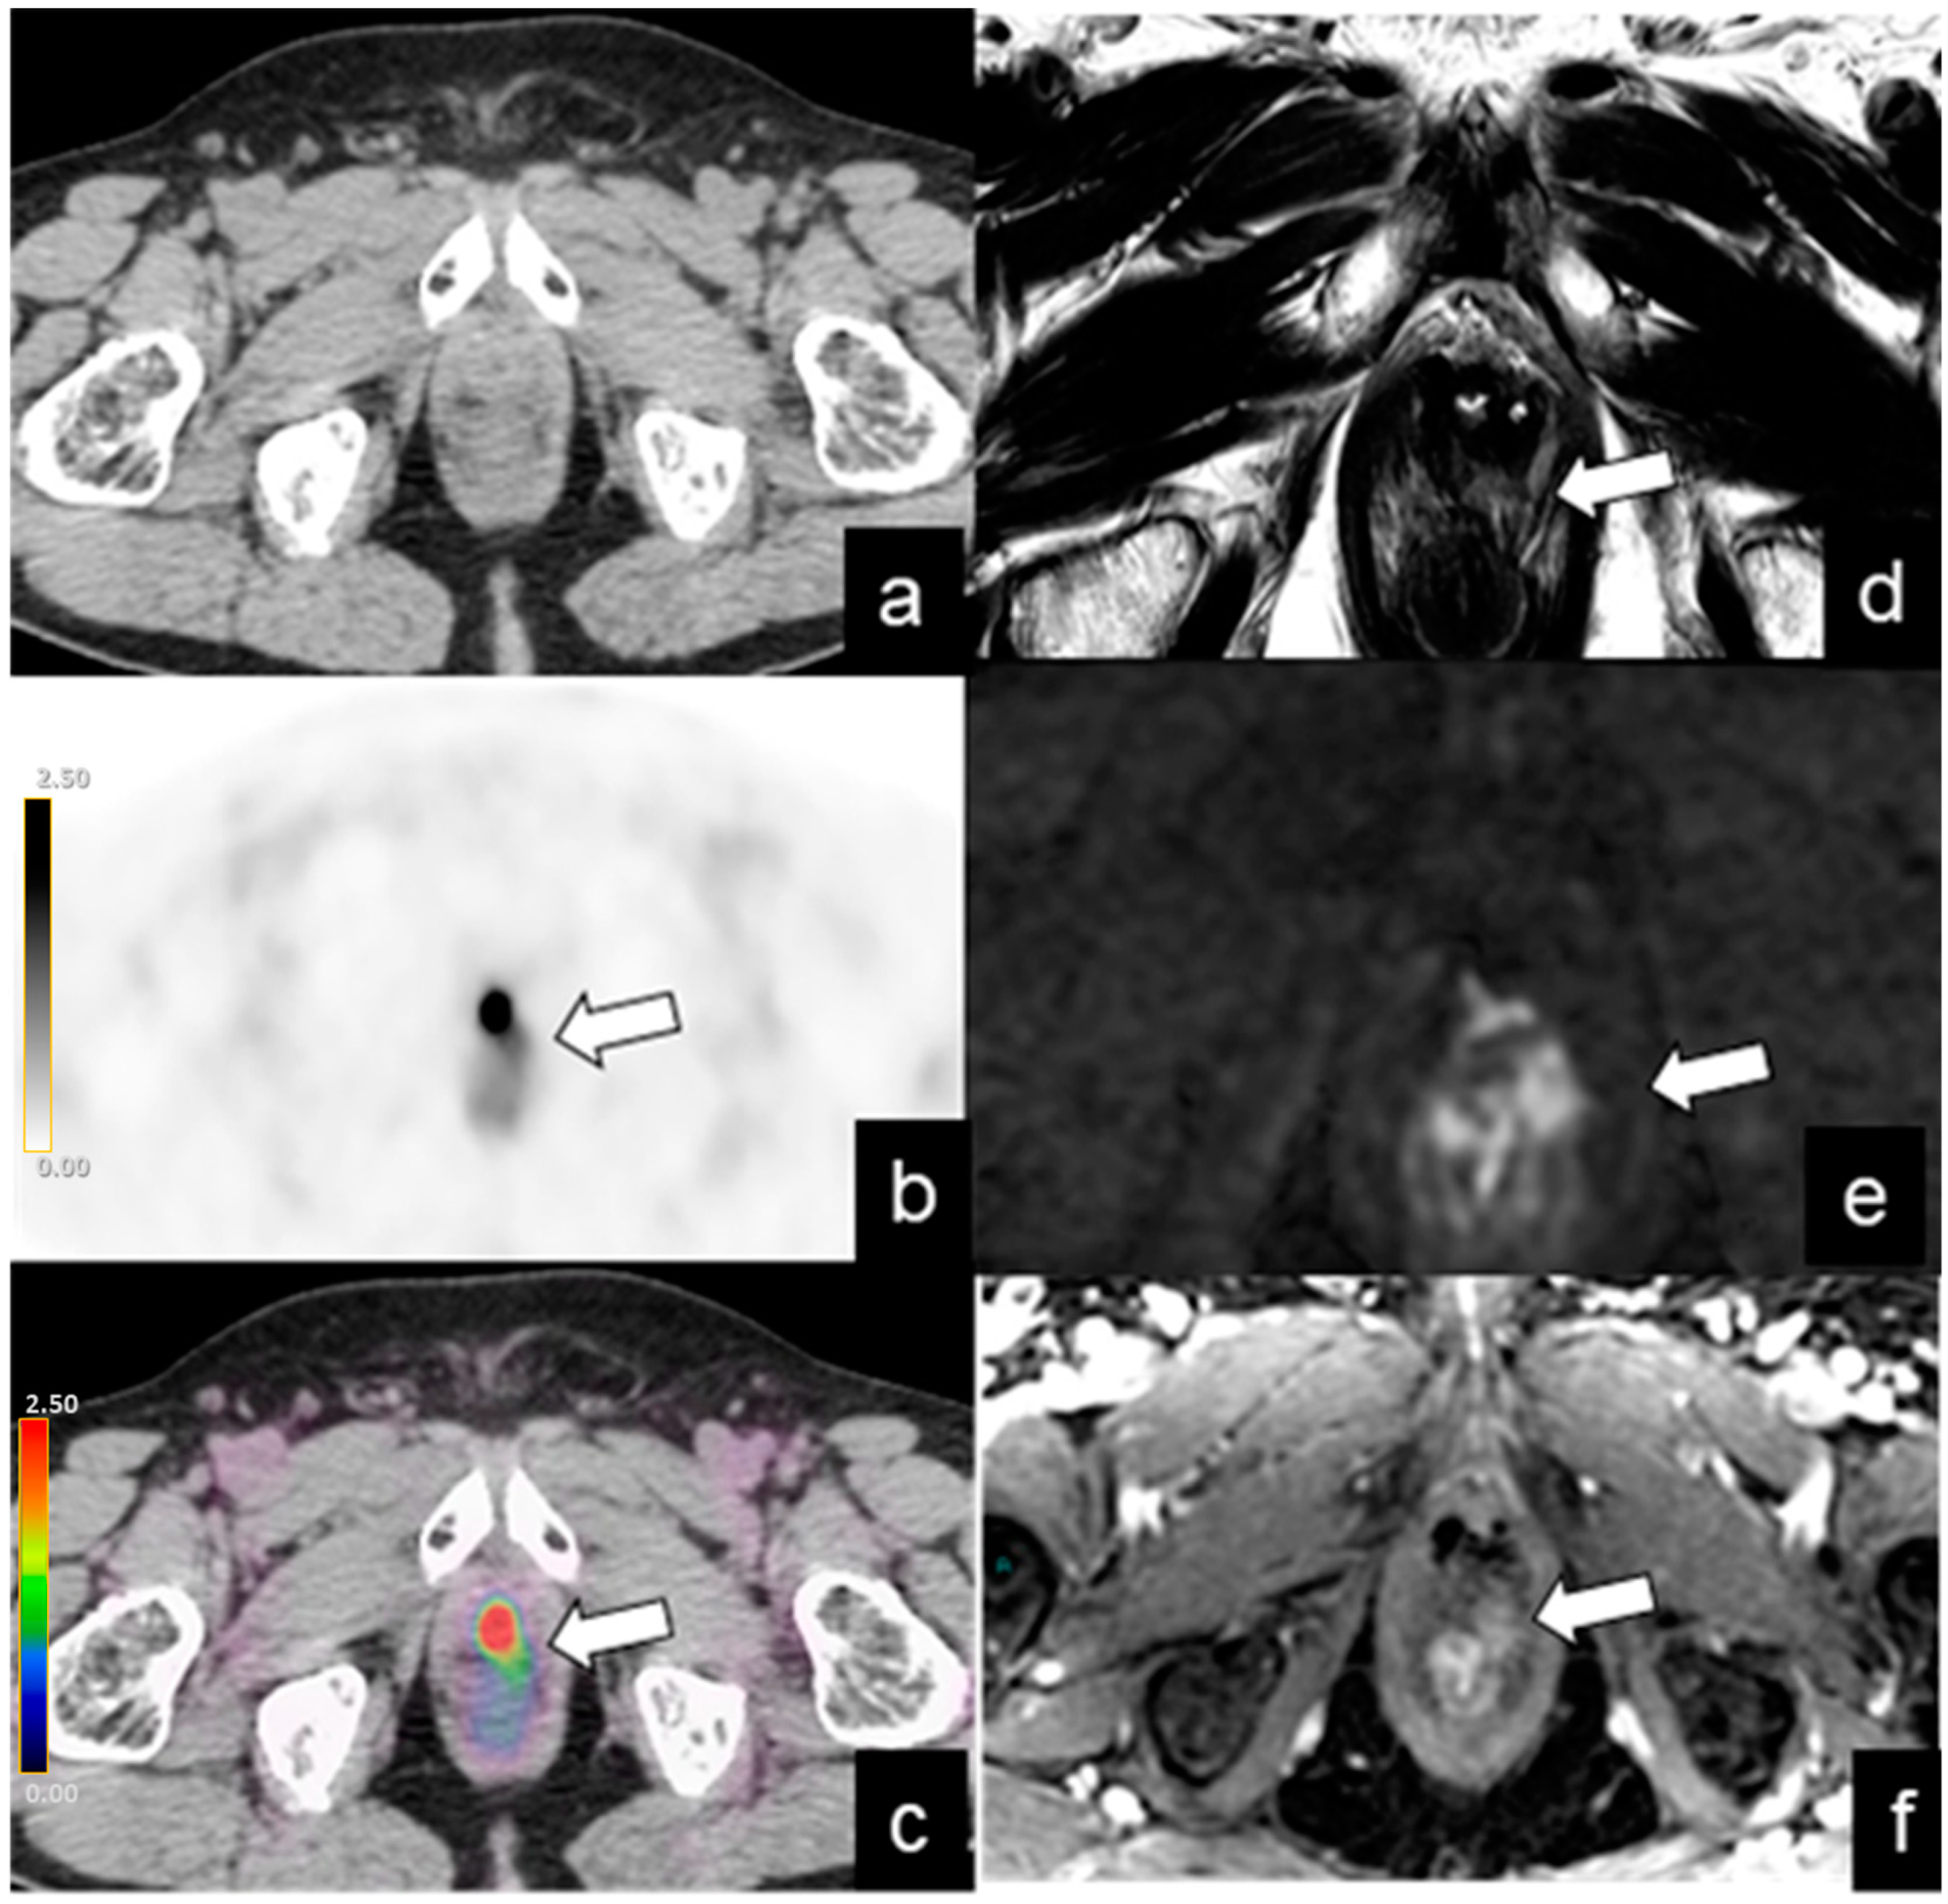

| Local recurrence | 42/128 (32%) | 12 | 2.1–46 | 9.6 | 3–53 |

| Lymph-node metastases | |||||

| Abdominopelvic | 39/128 (30%) | 24 | 1–73 | 7.3 | 2–19 |